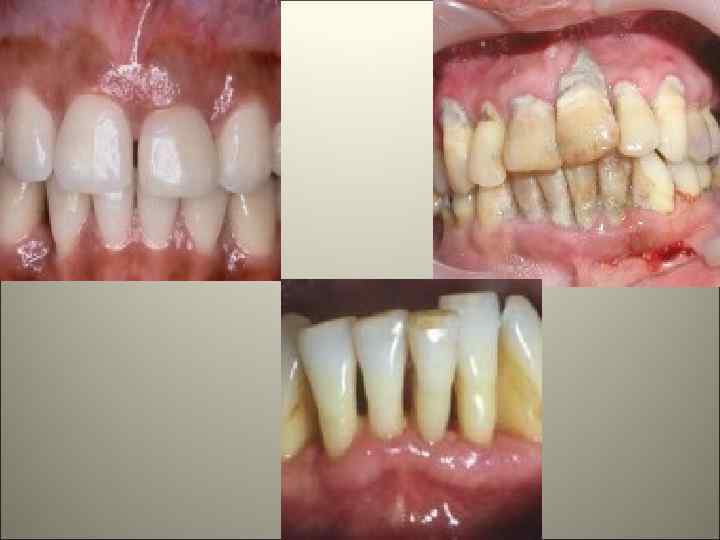

Маргинальный и генерализованный гингивит

4. По течению: острый, хронический и рецидивирующий. 5. По степени тяжести: - легкой степени – поражение межзубной десны; - среднетяжелой степени – поражение межзубной и маргинальной десны; - тяжелой степени – поражение всей десны, включая альвеолярную. При гипертрофическом гингивите: - легкая – десна прикрывает коронку зуба на 1/3; - среднетяжелая – десна прикрывает коронку до половины; -тяжелая – десна прикрывает коронку более чем на половину.